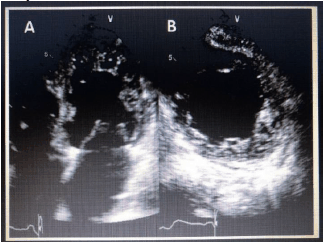

De acordo com a patologia presente na imagem adquirida abaixo, assinale a alternativa correta.

Médico - Ecocardiografia